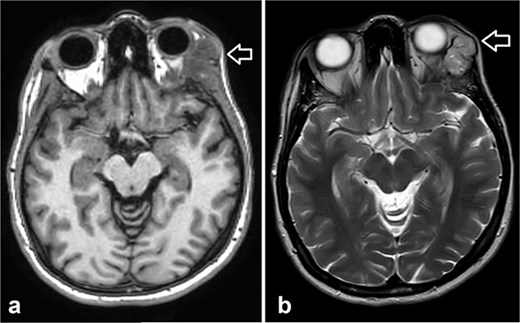

Orbit MRI showed a lobulated, well-defined lesion, hyperintense to intermediate on T2W (b) and hypointense on T1W (a) structures with cystic changes, measuring 2.3 × 1.9 cm and 2.6 × 1.6 cm, compared with the previous study, the lesions have increased in size.

MRI is the preferred modality to detect bony invasion and perineural spread. ACC usually appears as T1 isointense and T2 hyperintense with enhancement . Our patient's orbit MRI showed a lobulated, well-defined lesion, hyperintense to intermediate on T2W and hypointense on T1W structures with cystic changes.